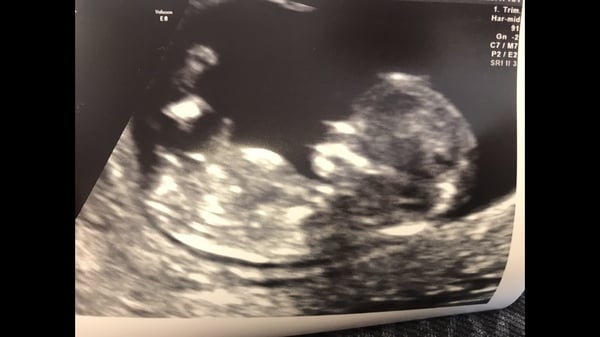

Thanks @Gem173 baby dug their bum right in so have so squashed pics... Took ages and a lot of wiggling to get the measurements, they didn't want to budge x

Gem173 · 10/02/2018 20:11

Wow that picture is so clear!! Your so lucky I’ve seen some pictures and they have not been as clear as that!